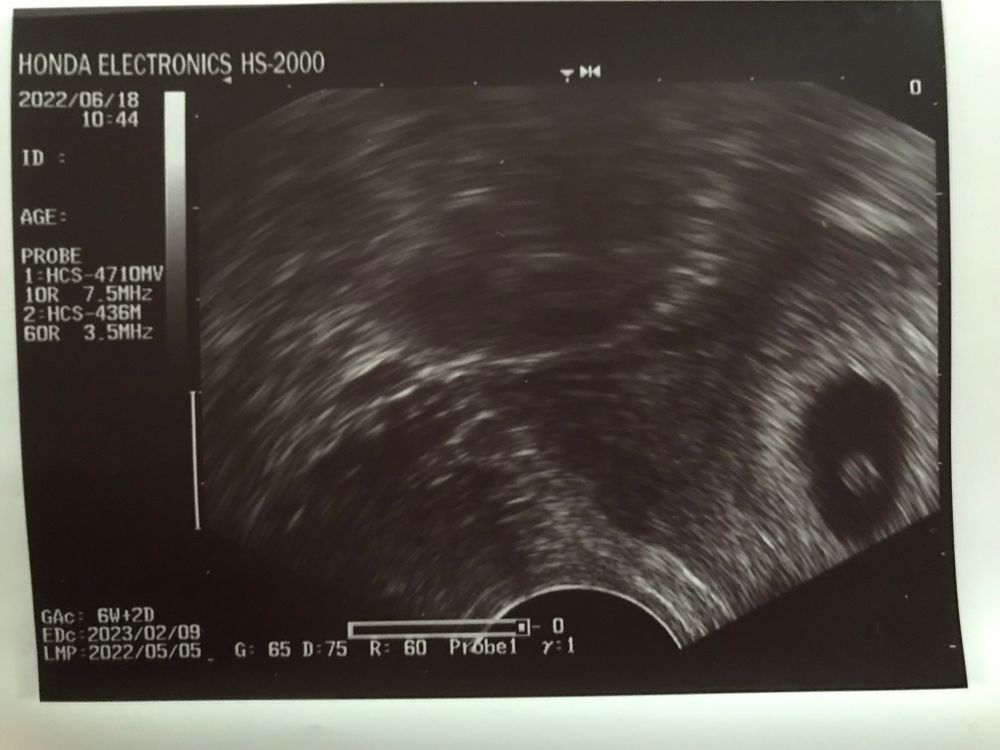

И так… 26 дпп мое узи

Успех с первой попытки 🥰🤰 Узи 21дпп при хгч 24000